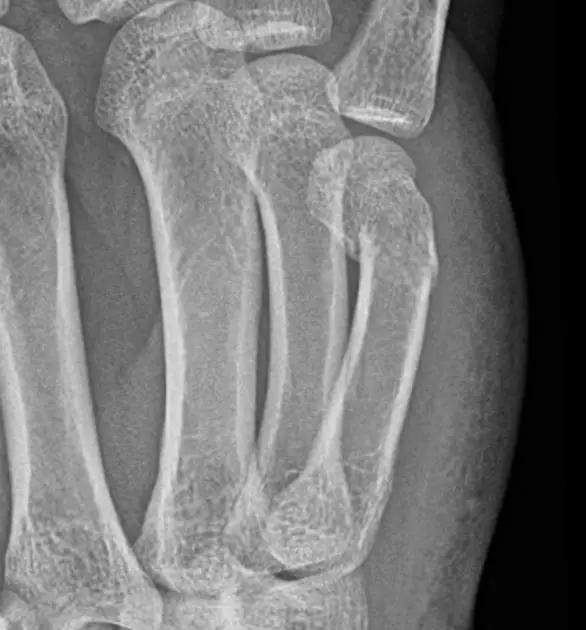

13. Lisfranc 骨折

骨折累及到足的跗骨关节。跖跗关节位于足的前部,是构成足纵弓及横弓的重要结构。

第一跖骨与第一楔骨组成鞍状关节,整个跖跗关节的稳定性,有赖于第一跖跗关节的稳定性,一旦第一跖跗关节发生脱位,其他 4 个跖跗关节容易发生脱位。第一跖跗关节的关节囊有背侧和跖侧副韧带增强,其内缘尚有胫前肌腱附着。第一、二跖骨基部无韧带相连,第一楔骨与第二跖骨基部间有坚韧的 Lisfranc 韧带相连,有助于第一跖跗关节的稳定性。第二楔骨较短,第二跖骨位于第一、二楔骨之间成为外力作用的支点。因此第二跖骨基底易发生骨折。

Lisfranc 关节复合体(Lisfranc joint complex)示意图:first metatarsal 第一跖骨;second metatarsal 第二跖骨;Lisfranc joint 利斯弗朗关节;first,second and third cuneiforms 第一,二,三楔骨;cuboid 骰骨